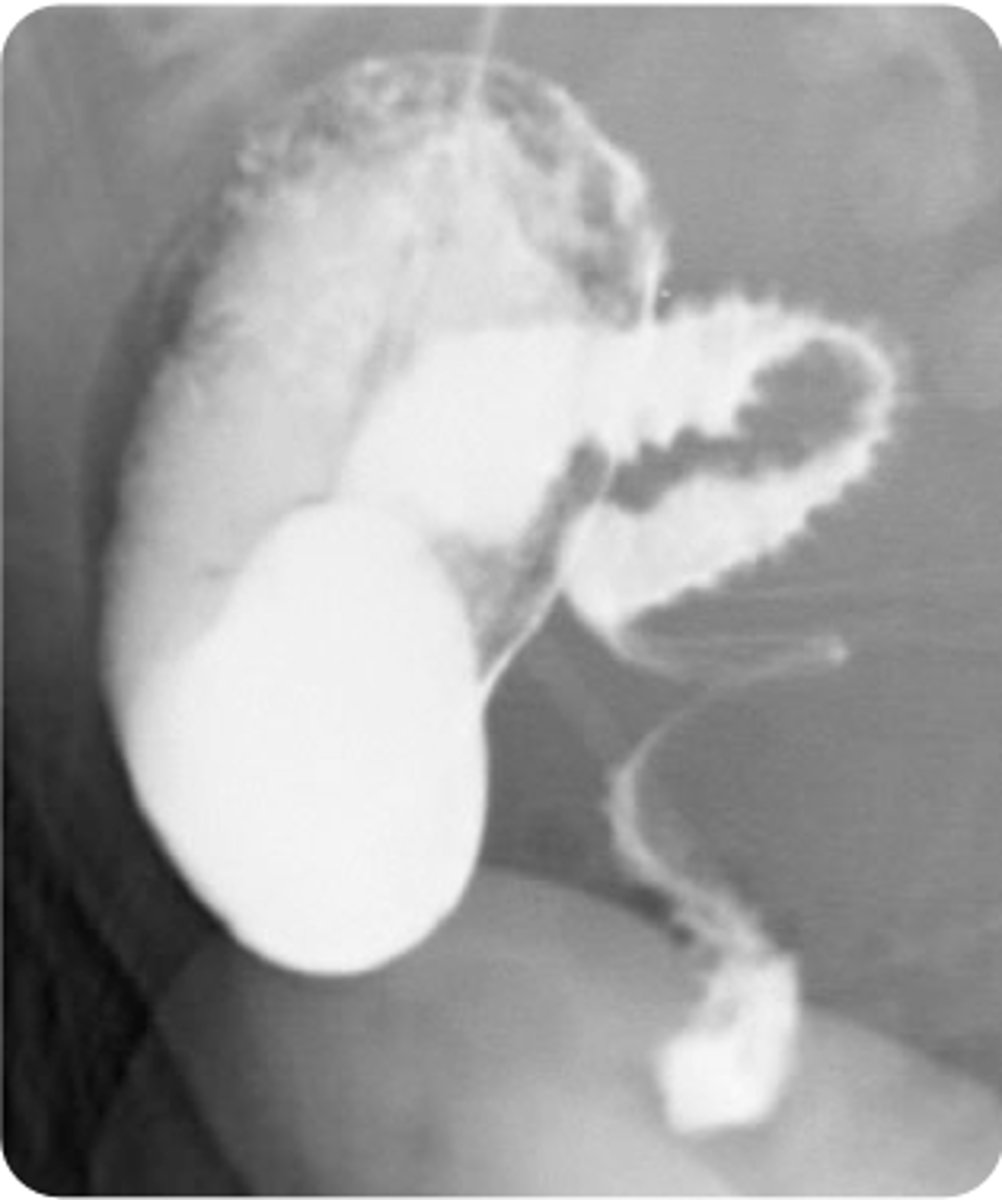

open surgical repair

**volvulus

A 1-month-old boy presents with his parents to the emergency department for evaluation of bilious vomit. His parents state that he has been crying and has been inconsolable since this morning. He began to have this type of vomit 2 hours ago. His parents report he has not had a bowel movement today. Vital signs are a blood pressure of 80/45 mm Hg, heart rate of 150 bpm, respiratory rate of 40/min, temperature of 99.2°F, and oxygen saturation of 100% on room air. On physical exam, his abdomen appears swollen and is tender to palpation. An upper GI series is obtained, and the results are shown above. What is the appropriate treatment option for this patient?

COpen surgical repair